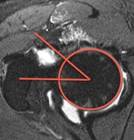

Knee Patella Malalignment

Knee Patella Malalignment AI

Automatic Diagnosis on X-ray. Measurement of Install-Salvati, Caton-Deschamps.

Aryan Kaul, Jason Pai, et al.